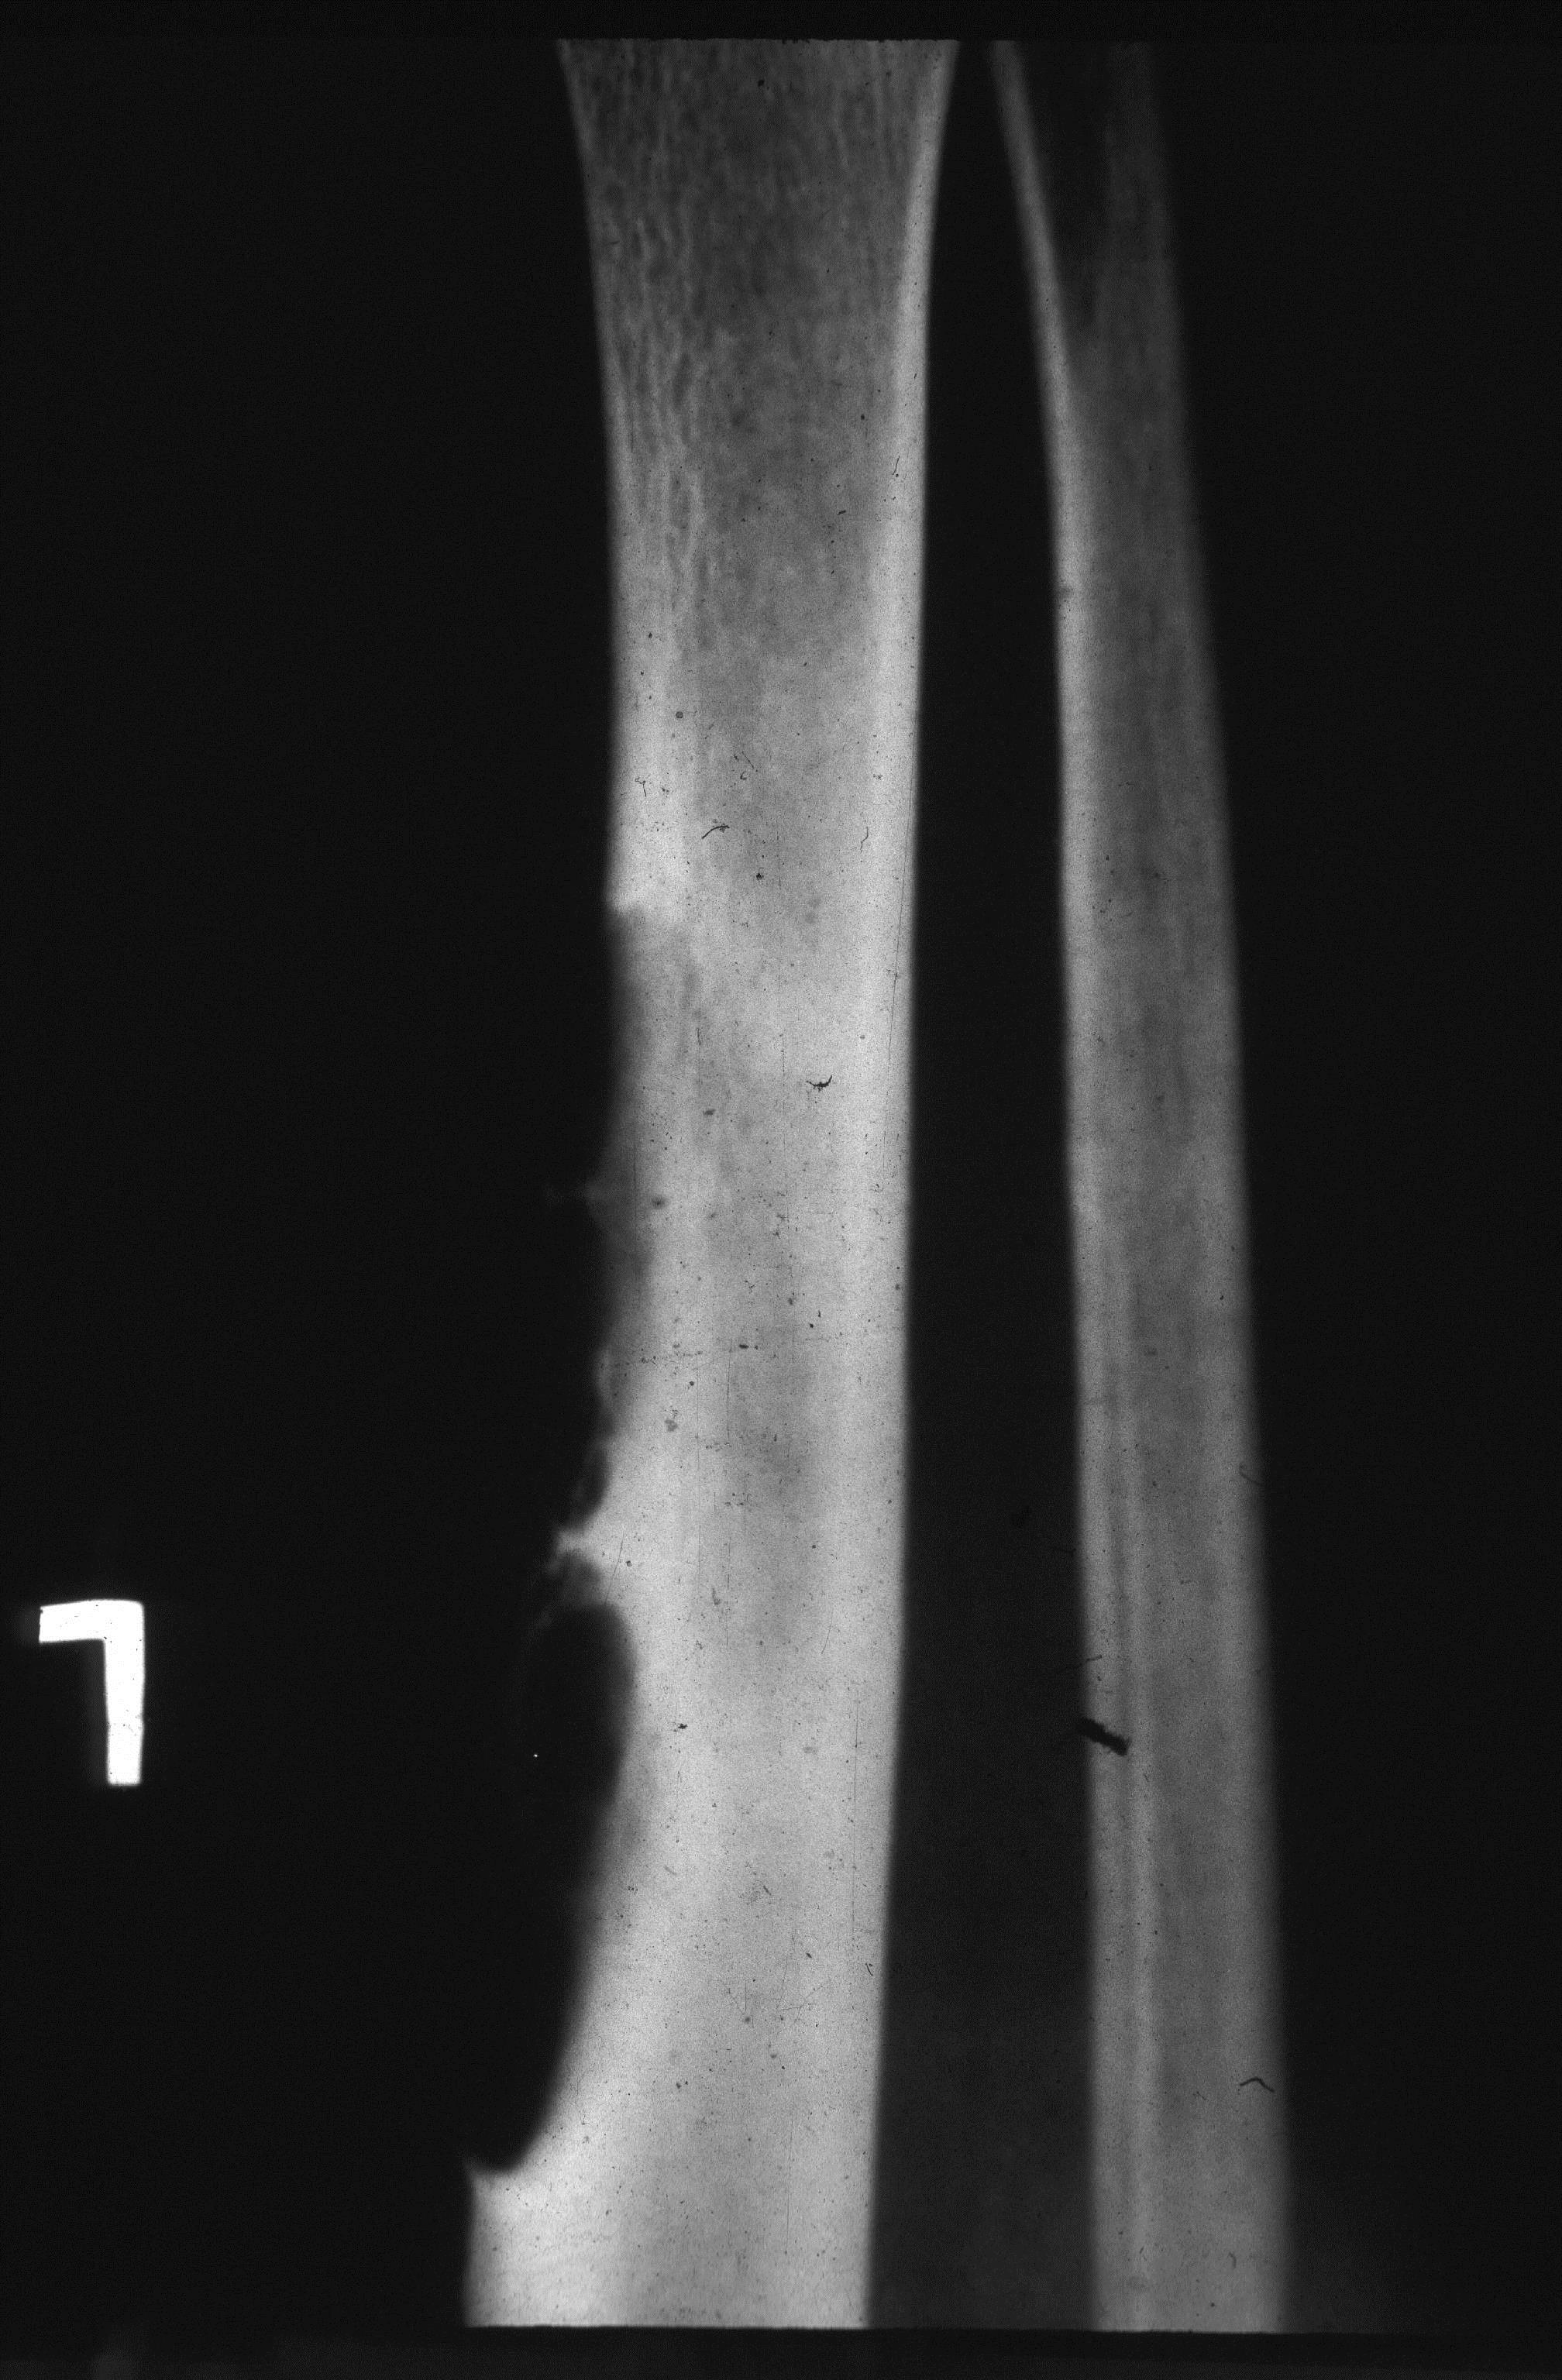

Generally occurs in children less than 10 years. Spontaneous regression is known. Any surgical correction leads to recurrence. Osteofibrous Dysplasia (OD) OD is another entity commonly involving the tibial shaft. Radiologically, an elongated lytic lesion with areas of sclerosis and anterior bowing of the tibia are classical features (Figure 2).

Figure 2a,b: Osteofibrous dysplasia of the tibia. Note the lytic and sclerotic changes scattered. Anterior bowing of the tibia is a characteristic finding.